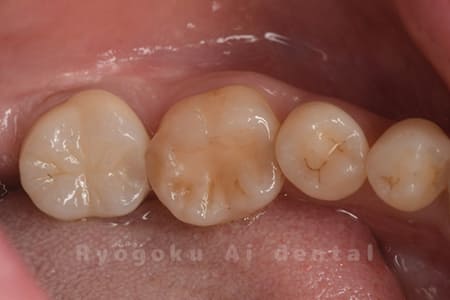

Case08

-

- 原因

- 虫歯

- 治療内容

- セラミックインレー

- 治療費用

- 77,000円

奥歯の黒い点が気になるということで来院された患者さんです。白い詰め物を外したところ、虫歯が中で大きく広がっていたため、患者さんと相談し、セラミックインレーで治療を行いました。

<リスク・副作用>

過度の咬合や衝撃で割れることがあります。